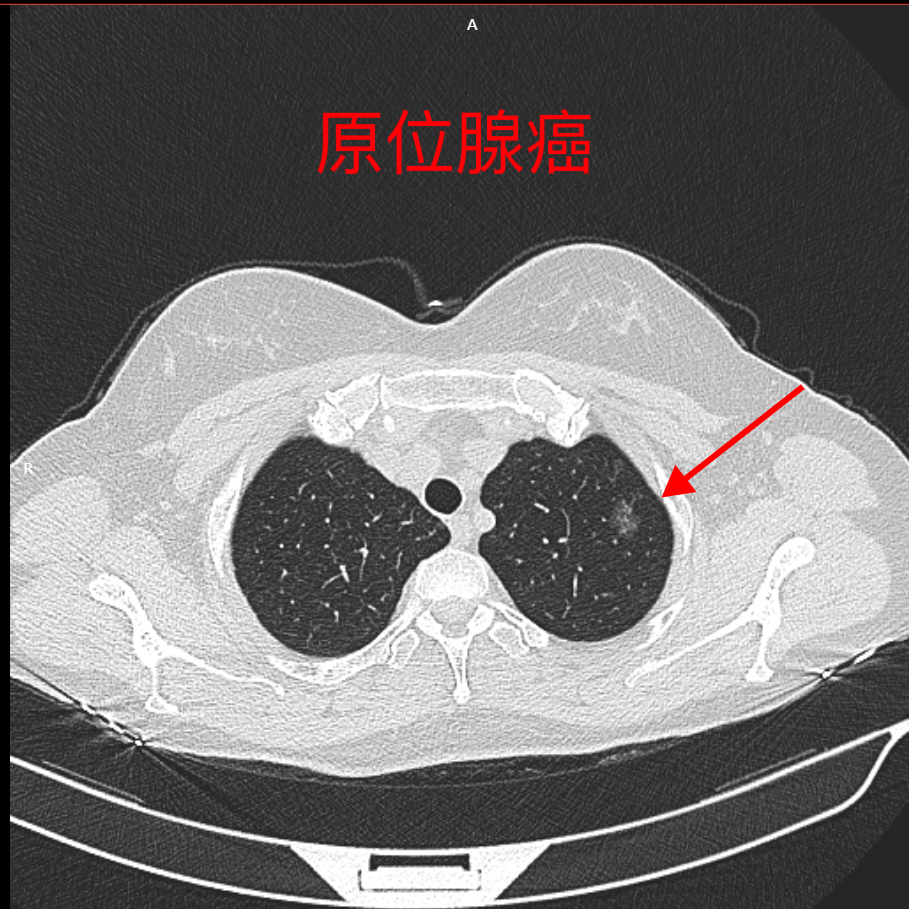

左肺上叶尖后段结节.#左肺上叶解剖 #左肺解剖 #左肺上叶楔